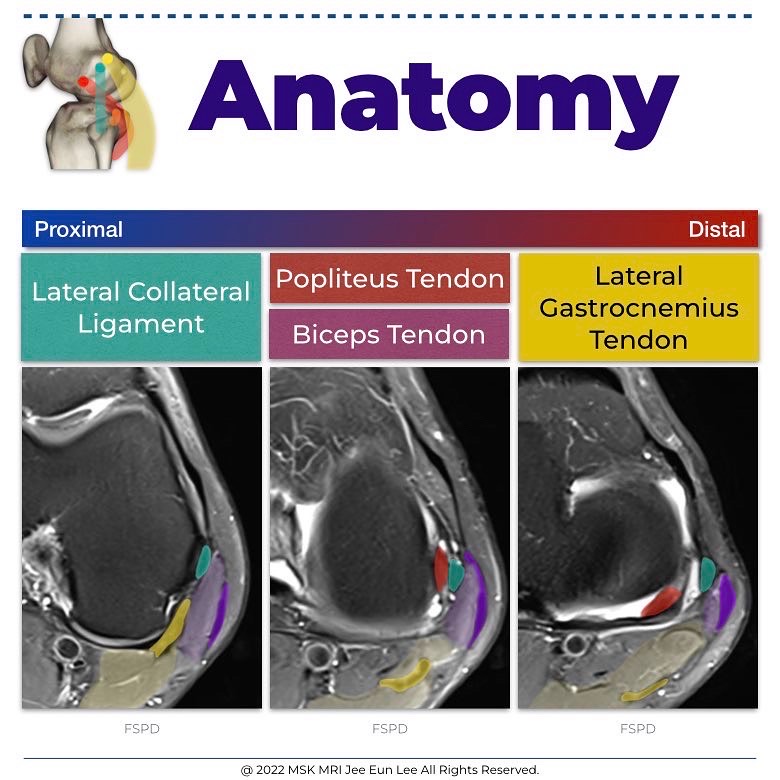

The popliteus musculotendinous complex—consisting of the popliteus tendon, popliteus muscle, and PFL

The tendon, which is intracapsular, but extra-articular and extrasynovial, ascends around the posterolateral aspect of the knee

The tendinous attachment lies anteroinferior to the proximal attachment of the lateral collateral ligament on the lateral epicondyle

The average distance between the femoral attachments of the popliteus tendon and fibular collateral ligament was 18.5 mm.

- Lateral collateral ligament

The fibular collateral ligament, or lateral collateral ligament, originates from the distal femur in a fanlike fashion between the lateral epicondyle and supracondylar process (attaching just proximal and posterior to the lateral epicondyle), and directly anterior to the lateral head of the gastrocnemius muscle.